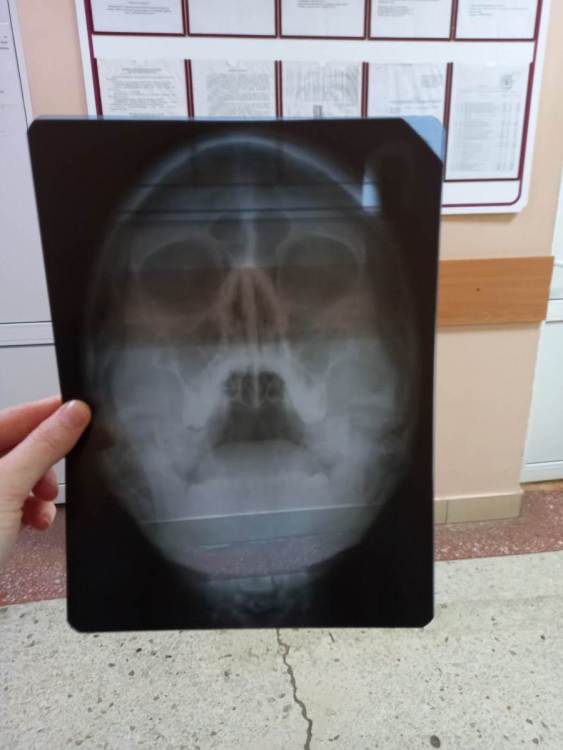

Mariaduya Опубликовано 5 июля, 2023 Поделиться Опубликовано 5 июля, 2023 (изменено) Здравствуйте. У меня сложная ситуация, боли в челюсти практически 1.5 года. Врачи не видят проблем, уже не знаю куда обратиться. Хронология. 1. В ноябре 2021 начал слегка болеть 1.6 зуб. В стоматологии мне его сразу начали депульпировать, без снимка. В ходе лечения не болел, как запломбировали каналы, постепенно появилась ноющая, постоянная боль. Я обратилась снова, сказали, что на зубе есть хроническое воспаление и ввели антибиотик туда при помощи электрофареза. Среагировал 2.5 зуб с другой стороны, и тоже начал постоянно болеть, он был депульпирован давно, но в нем развился большой кариес. 2. Мне начали их перелечивать. 1.6. не получилось пройти канал, залили резодентом, 2.5 просто переличили. 3. Боль все ещё осталась, уже в двух зубах. Врачи ничего не знают, отправили к неврологу, ЛОРУ и т.д. 4. Обошла неврологов, лоров, делала мрт, кт с контрастом головы, пазух носа, все ок. Невролог выписывает финлепсин, не помог. 5. Делала в частной клинике кт зубов, без описания, ещё не знала, что оно нужно, врач посмотрела и сказала, что видит небольшое, хроническое воспаление на 1.6 зубе и все, а так она не знает. 6. И так 1.5 года никто не знает, что со мной. Боль 1.6 и 2.5 зубы, начинают и нижние зубы болеть, уже и ухо болит. После орви болит все очень сильно, что хочется уже не просыпаться. Удалять их говорят не показаний, вдруг боль останется. Снимки в хронологии выкладываю. Есть ли на них воспаление 1.6 зуба, 2.5 зубов, есть ли них кисты свищи и все что угодно, что аномально и может вызывать боль. Может что-то с надкостницой, или суставами. Все что у меня есть - интернет, так как живу я очень далеко от нормального города и доступна только городская поликлиника, где врачи говорят, что это неврология, а невролог говорит наоборот. Сами зубы болят странно, по очереди. Если болит неделю 1.6 зуб, то 2.5 не болит и так наоборот. Вместе они не болят. Ещё странное то, что они практически симметричны друг другу по расположению. Изменено 5 июля, 2023 пользователем Mariaduya Ссылка на комментарий

Carioznik Опубликовано 5 июля, 2023 Поделиться Опубликовано 5 июля, 2023 Здравствуйте, 27 зуб надо внимательнее посмотреть, возможно там пульпит (но это неточно "бумажные " снимки малоинформативны). Скиньте лучше КТ или хотя бы ОПТГ но в электронном формате(а не фото распечатки на бумаге) Ссылка на комментарий

Carioznik Опубликовано 13 июля, 2023 Поделиться Опубликовано 13 июля, 2023 по этому старому КТ: на 16 - есть пропущенный канал, от этого, на одном из корней - есть небольшой воспалительный процесс (на тот момент). "Само не заживет", будет только расти, может, на сегодняшний момент - уже стал большой). Но жалобы в таких случаях обычно другие. Делайте новое КТ (по старому только гадать...) и снова, очный осмотр стоматолога, явно понадобится. 1 Ссылка на комментарий